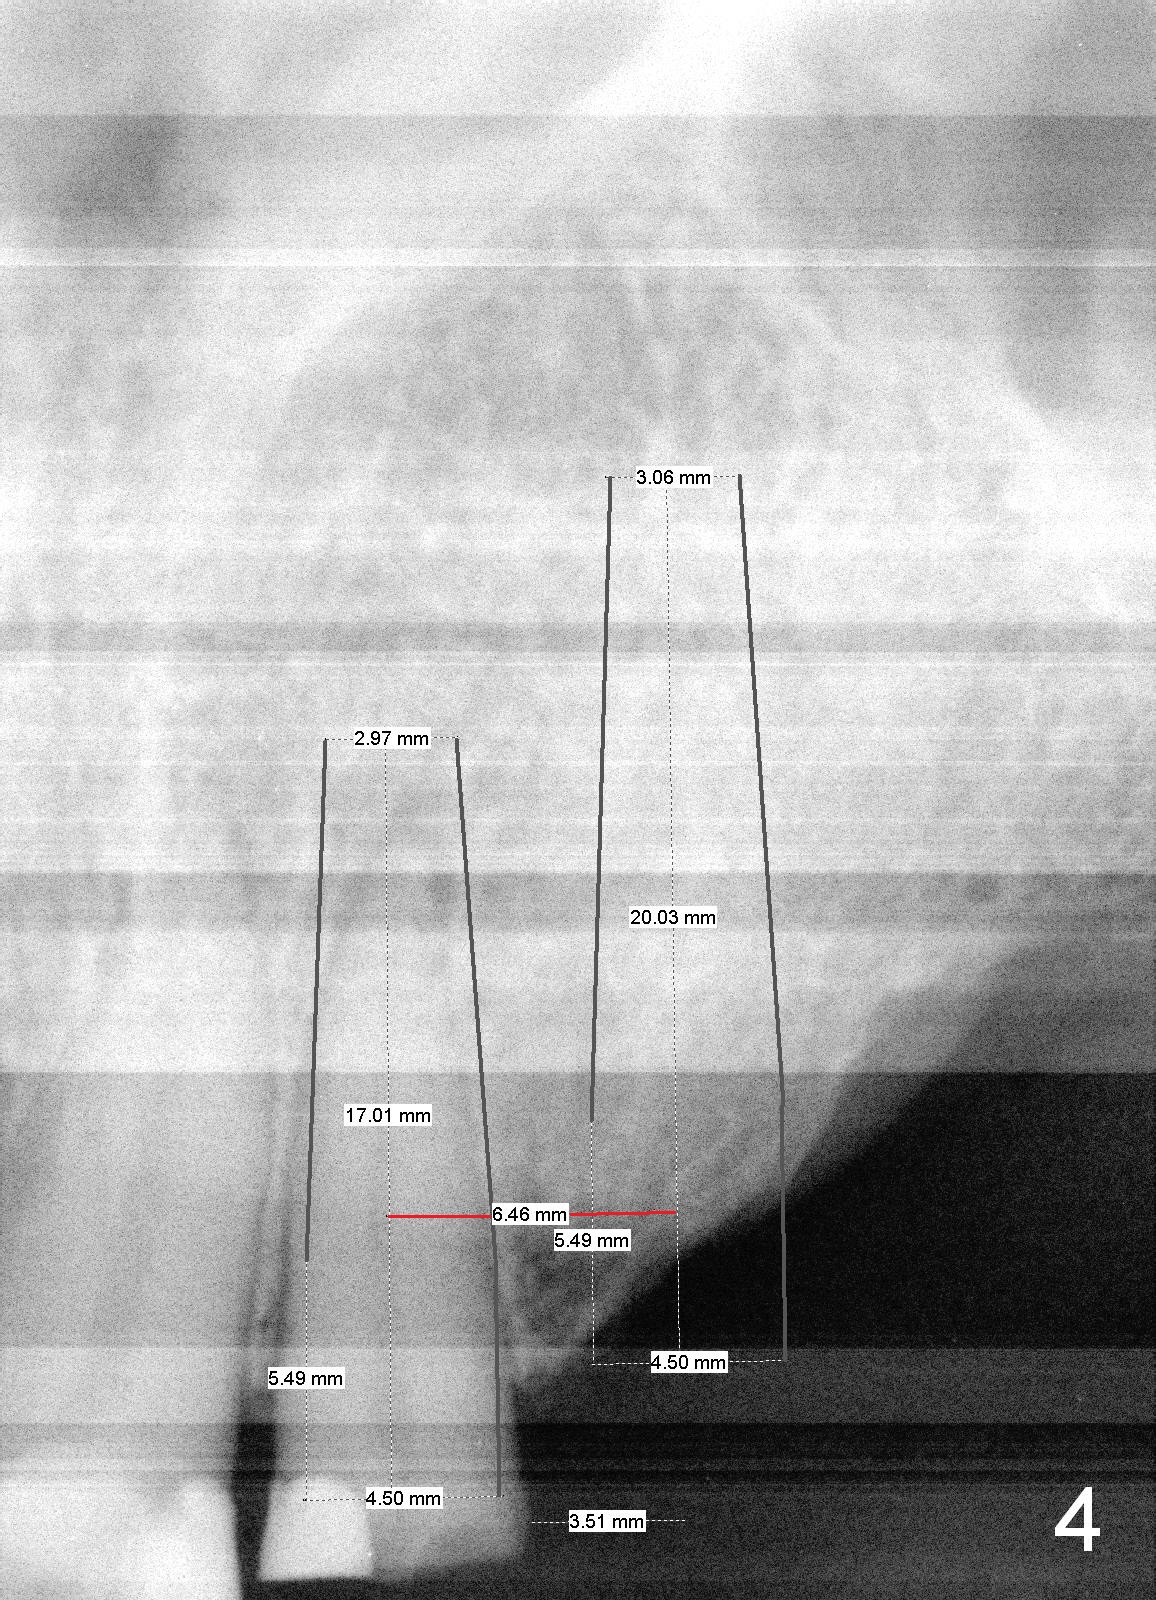

A 70-year-old man (TF) requests implant restoration for the upper left quadrant first (Fig.1), exactly #10 and 11 first (Fig.2-4). There is periapical radiolucency associated with the residual root at #10 (Fig.2 *). Local antibiotic will be Metronidazole. The root of #10 is long and large. The bone at #11 looks loose. Long implants will be placed (Fig.4). Osteotomy preparation should be less.